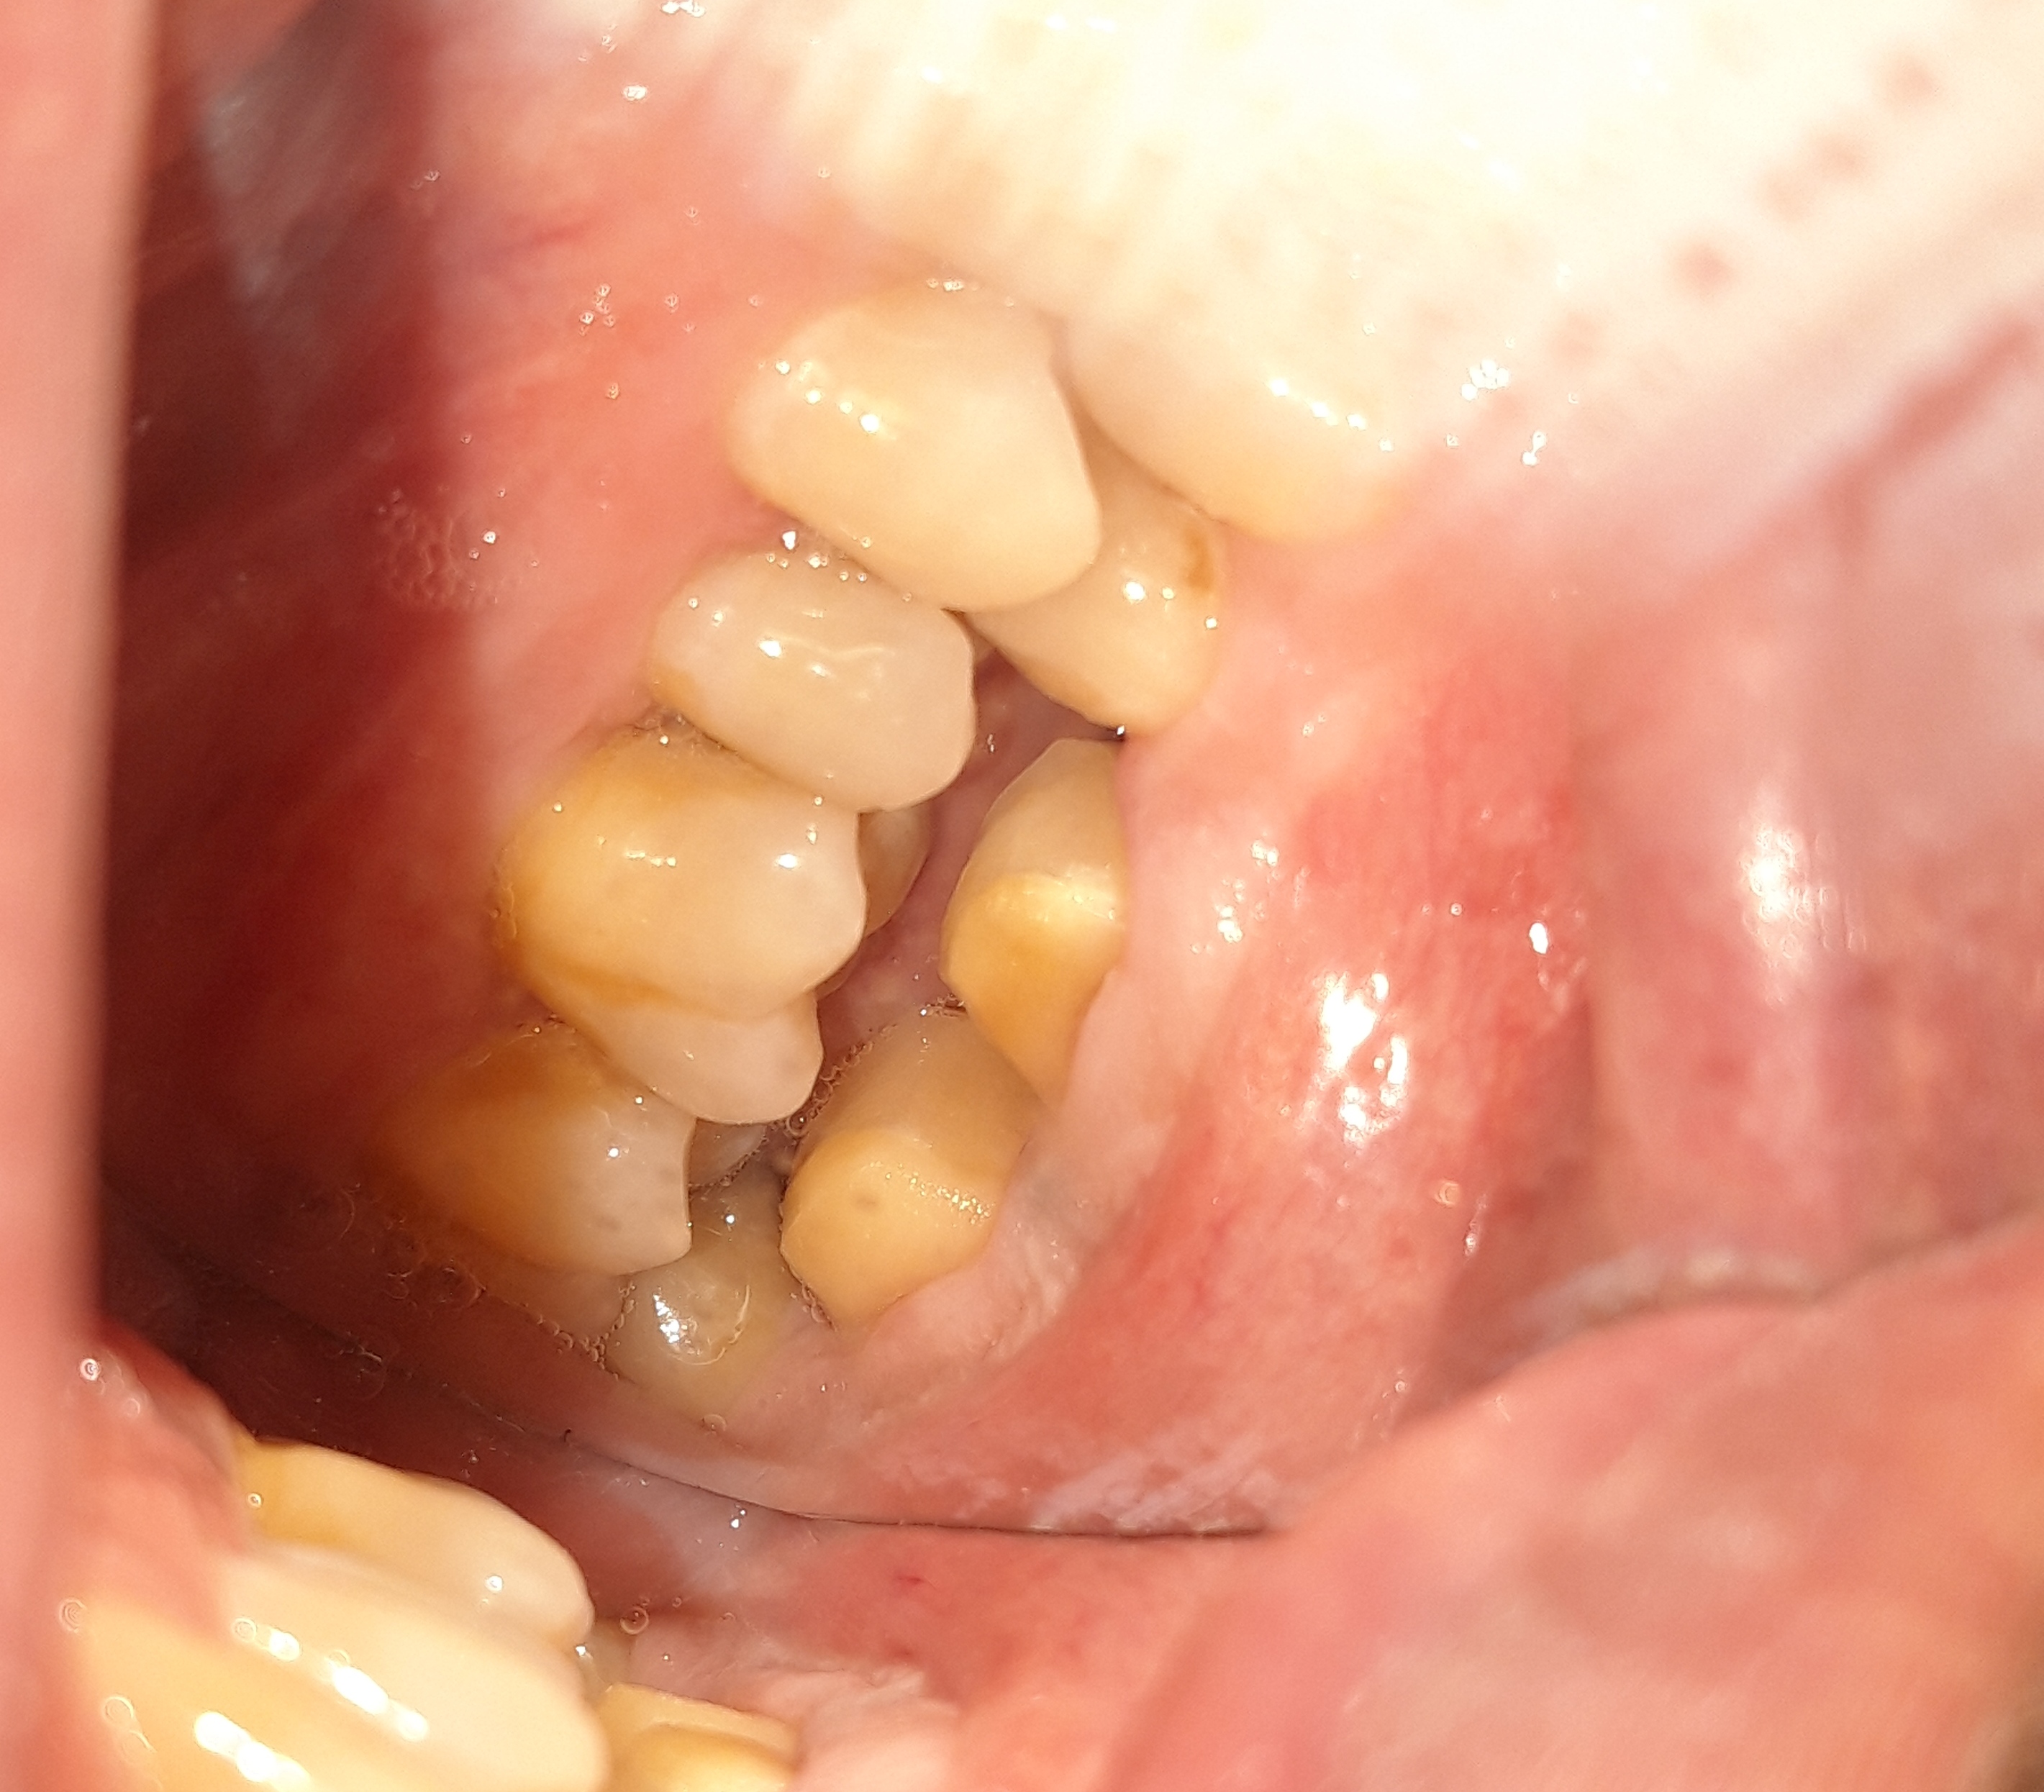

Ο πρώτος γομφίος στην αριστερή πλευρά της άνω γνάθου είχε ένα παλιό επνανατερηδονισμένο λευκό σφράγισμα. Αποφασίστηκε η αφαίρεση του παλιού σφραγίσματος και η αποκατάσταση του δοντιού με ολοκεραμικό ένθετο. Επειδή από το δόντι απουσίαζε μεγάλο μέρος οδοντικών ιστών η λύση επιλογής ήταν η τοποθέτηση ολοκεραμικού ένθετου, γιατί έχει μεγαλύτερη αντοχή στις μασητικές δυνάμεις και επομένως έχει μεγαλύτερη ανθεκτικότητα έναντι των θραύσεων στο πέρασμα των χρόνων.

Ο ασθενής αισθάνεται το δόντι του πολύ σταθερό και γερό.

Αρχική εικόνα του παλιού μεγάλου σφραγίσματος